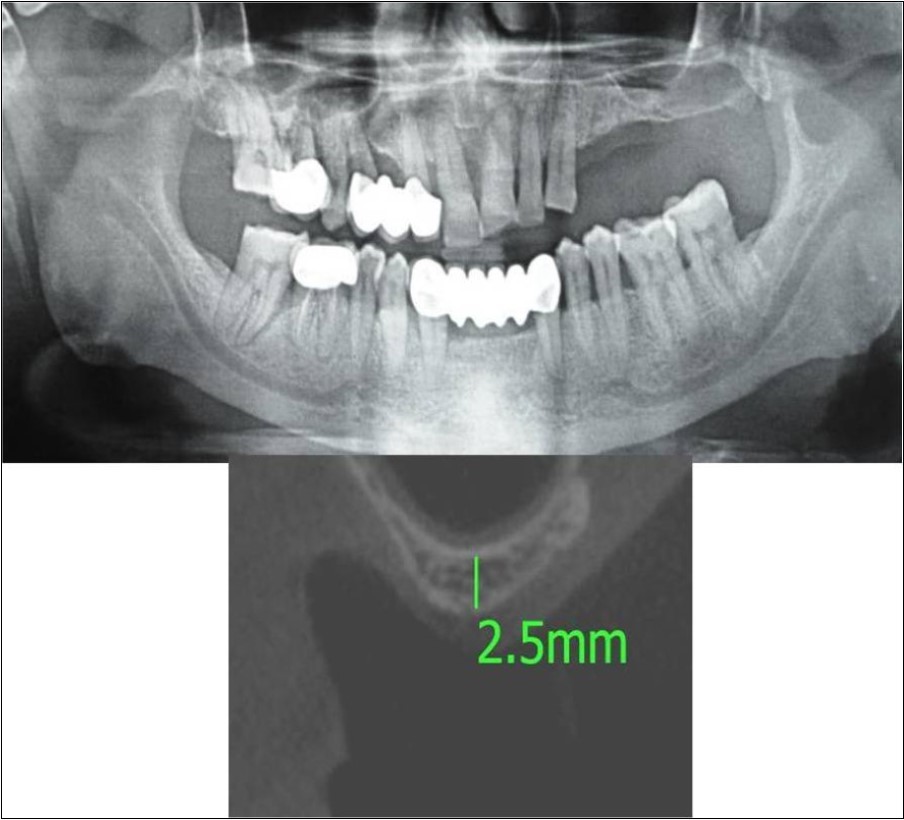

Case Report 1:

A 40 years old male patient reported to the Department of Oral and Maxillofacial Surgery, D.A.P.M.R.V Dental College and Hospital with a chief complaint of inability to chew food because of loose teeth from past one year. The teeth were extracted an year ago in the right upper and lower back tooth regions because of gross loss of tooth structure and poor prognosis for root canal treatment. Patient was a controlled diabetic and was on medication for the same. Patient did not give history of any existing sinus pathologies. All possible rehabilitative options were explained to the patient and a treatment plan of replacement of missing teeth with implant supported prosthesis using two dental implants was finalized.

Clinical and Radiological Assessment:

1.Partially edentulous maxillary and mandibular arches with missing 16, 17, 18, 46, 47, 48;

2.Increased pneumatisation of right maxillary sinus;

3.Chronic generalized periodontitis;

4.Inter-ridge space adequate to place implant (25mm).

Treatment: Direct sinus augmentation using calcium phosphosilicate (CPS) in relation to 16,17 followed by implant placement as a single step procedure was advised. Lateral window was created and calcium phosphosilicate putty (2cc) was dispensed as the graft material through the lateral osteotomy site to maintain the elevated sinus membrane followed by placement of two dental implants through the crestal approach measuring 3.75 x 11.5mm under local anaesthesia and strict aseptic protocols. At the end of 6 months, a repeat CBCT scan was advised to evaluate the increase in bone height. (Figure 7a-c, pre-treatment; Figure 8a-c, post-treatment)

Figure 7.(a-c) Pre-treatment OPG and cross sections of CBCT showing residual alveolar bone height for Case No.1;

Figure 8.(a-c) Post-treatment OPG and cross sections of CBCT showing residual alveolar bone height for Case No.1;

Clinical and Radiological Assessment:

1.Partially edentulous maxillary arch with missing 24, 25, 26, 27, 28;

2.Increased pneumatisation of left maxillary sinus;

3.Height of available bone- 2.5mm;

4.Transverse thickness of available bone (CBCT evaluation)- 10.9mm;

5.Inter-ridge space adequate to place implant (12mm).

Treatment:

Patient underwent the procedure of direct sinus elevation using sinus lateral approach kit. After crestal and vertical release incisions, muco-periosteal flap was raised to expose the buttress region. A bony window of 1cm diameter was created; sinus lining identified and elevated up to receive calcium phosphosilicate as graft material and closure was achieved under local anaesthesia and strict aseptic protocols. Implant placement was planned to be carried-out after a period of 6 months to allow for the consolidation for graft and naive bone formation. At the end of 6 months, a repeat CBCT scan was advised to evaluate the increase in bone height. (Figure 15a,b, pre-treatment; Figure 16a,b, post-treatment)

Figure 15.a,b. Pre-treatment OPG and cross section of CBCT showing residual alveolar bone height for Case No.5;

Figure 16.a,b. Post-treatment OPG and cross section of CBCT showing residual alveolar bone height for Case No.5;